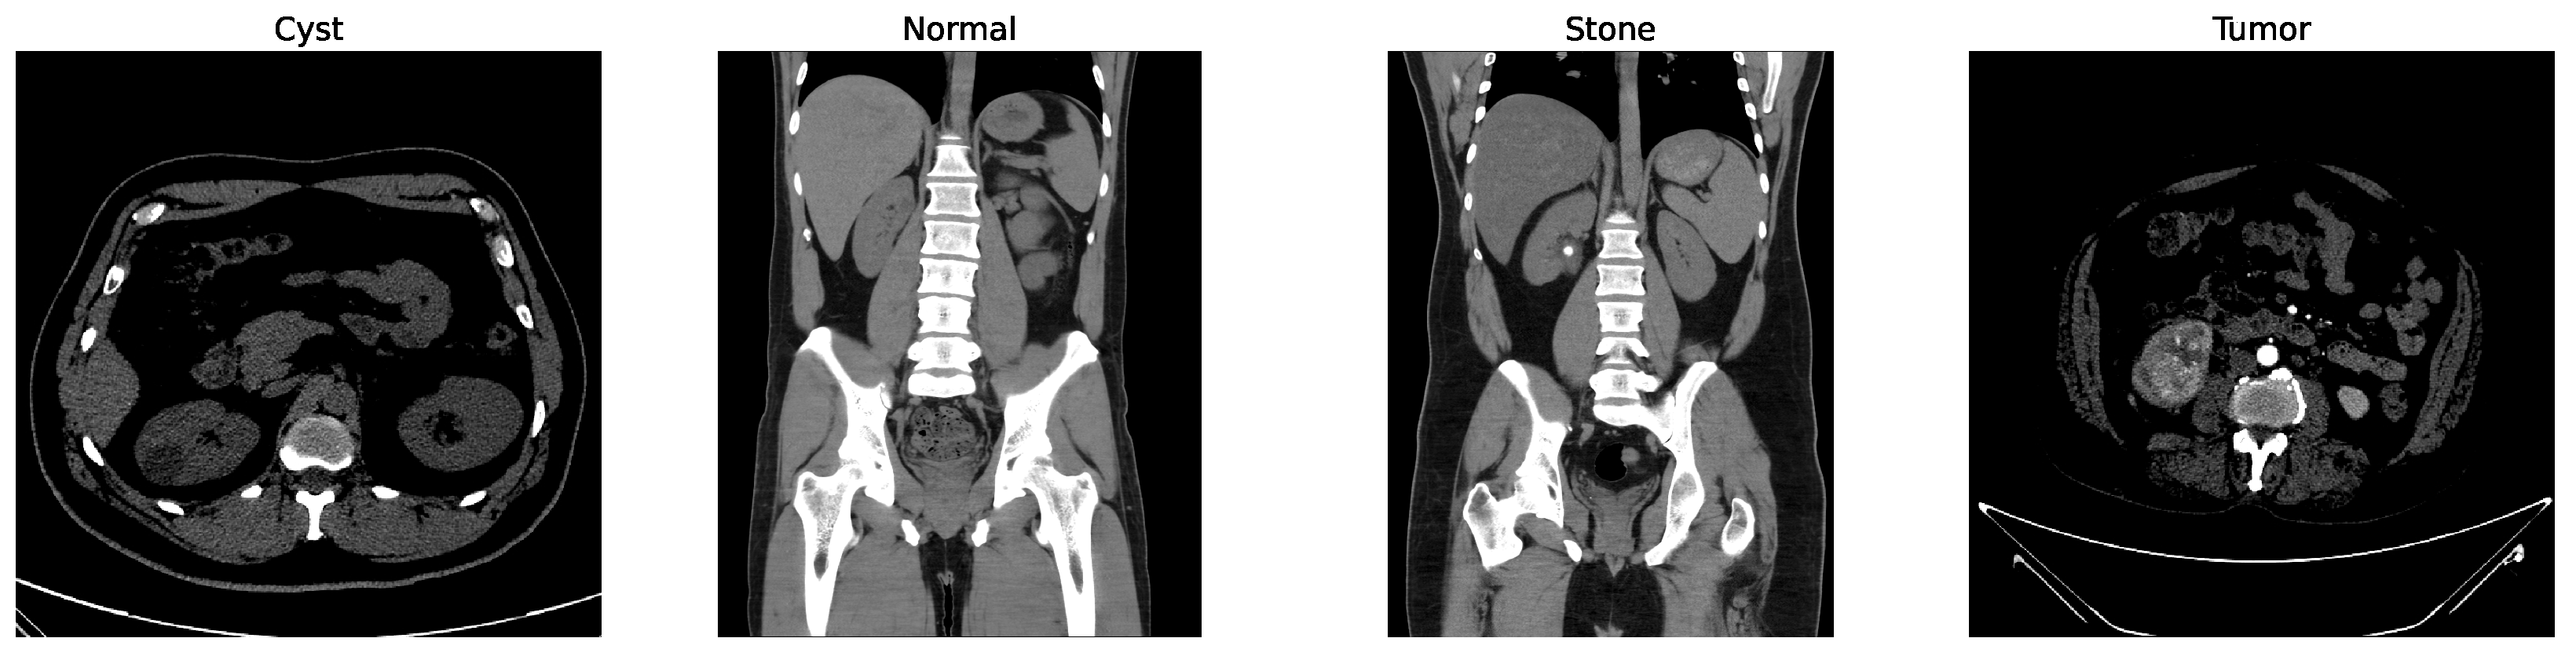

Some of the examples of the ct images of four classes are shown in Figure 3.

Figure 3.

Examples of cyst, normal, stone, and tumor CT image.